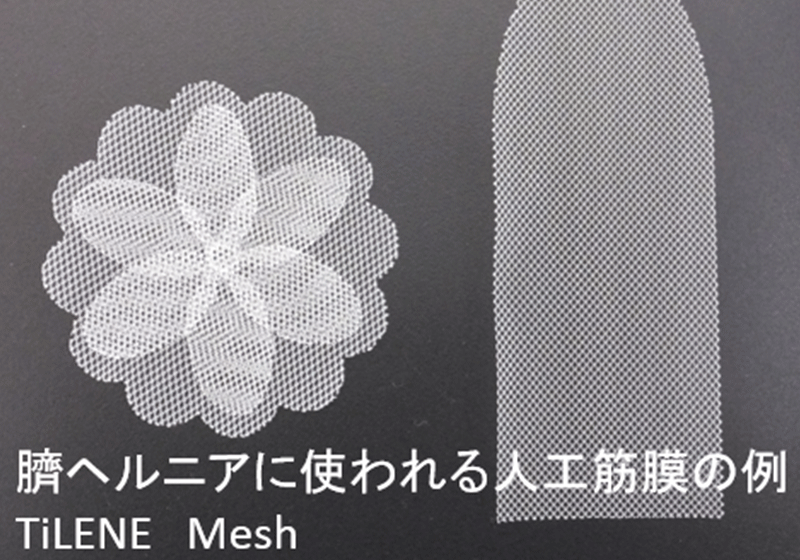

② 人工物(メッシュ)の留置

人工物(メッシュ)は、ヘルニア門の大きさや留置する部位により、数種類の中から選んで使用します。

③ 人工物(メッシュ)の留置

腹腔内からの観察した様子などから、最適な部位に人工物(メッシュ)を留置します。人工物(メッシュ)は、ヘルニア門の大きさや留置する部位により、数種類の中から選んで使用します。